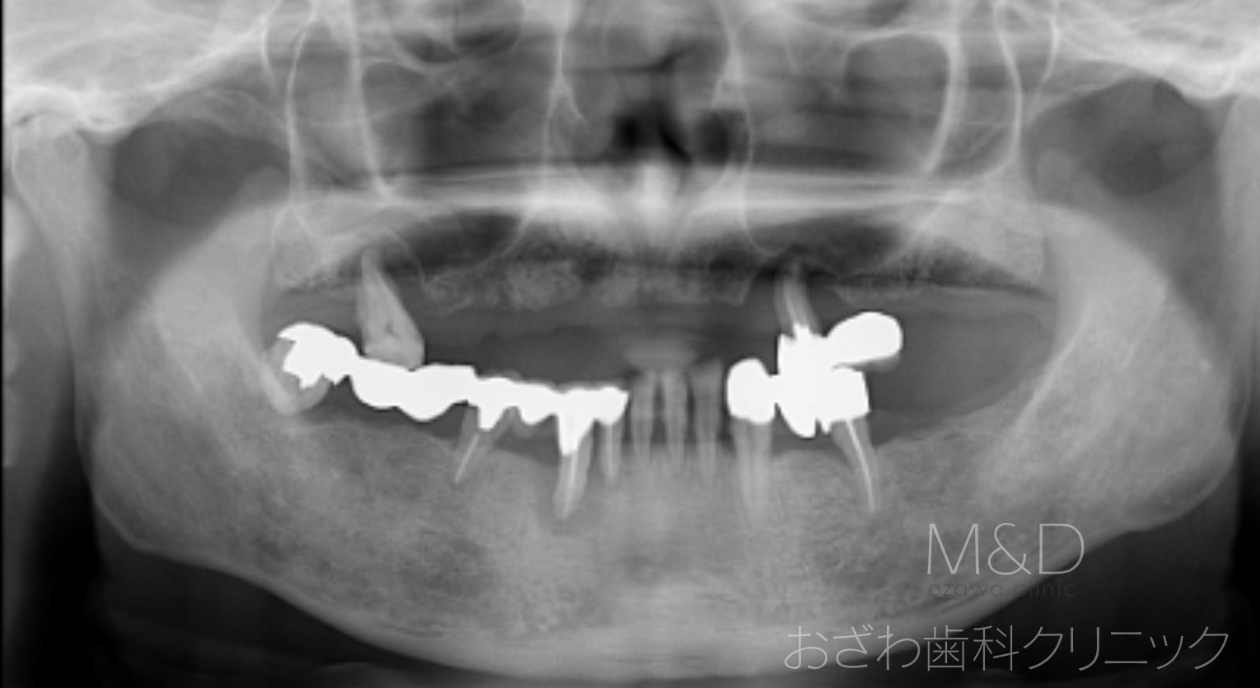

術前

主訴:上下の歯がぐらぐらして噛めない

治療内容

上下顎残存歯の抜歯、上顎6本、下顎6本インプラント